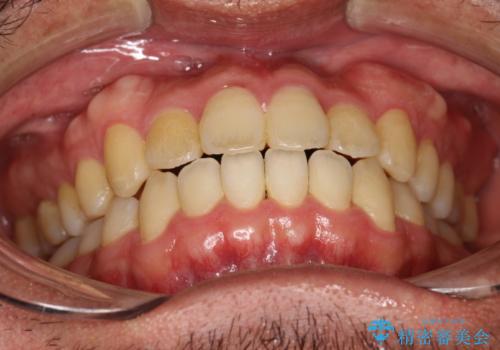

前歯が反対にかんでいる インビザラインとワイヤーを組み合わせた矯正治療

- 1年1ヶ月

- 約95万円費用は治療当時の料金となります

マウスピースのみでの治療も可能でしたが、治療期間がもう少し延長していた可能性があります。